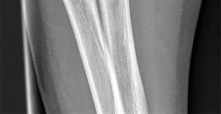

A 3-year-old boy sustains a closed, isolated, midshaft femur fracture after a fall from a playground structure.

Radiographs show 1.5 cm of overriding. What is the most widely accepted definitive management for this patient?

Question 32

An 8-year-old, 35 kg boy sustains a transverse midshaft fracture of the right femur. He is treated with titanium elastic nails (TENs). What is the most common complication associated with this surgical treatment?

Question 47

A 3-year-old boy sustains an isolated midshaft femur fracture. Radiographs demonstrate 1.5 cm of shortening and 10 degrees of varus angulation. What is the most appropriate definitive management?